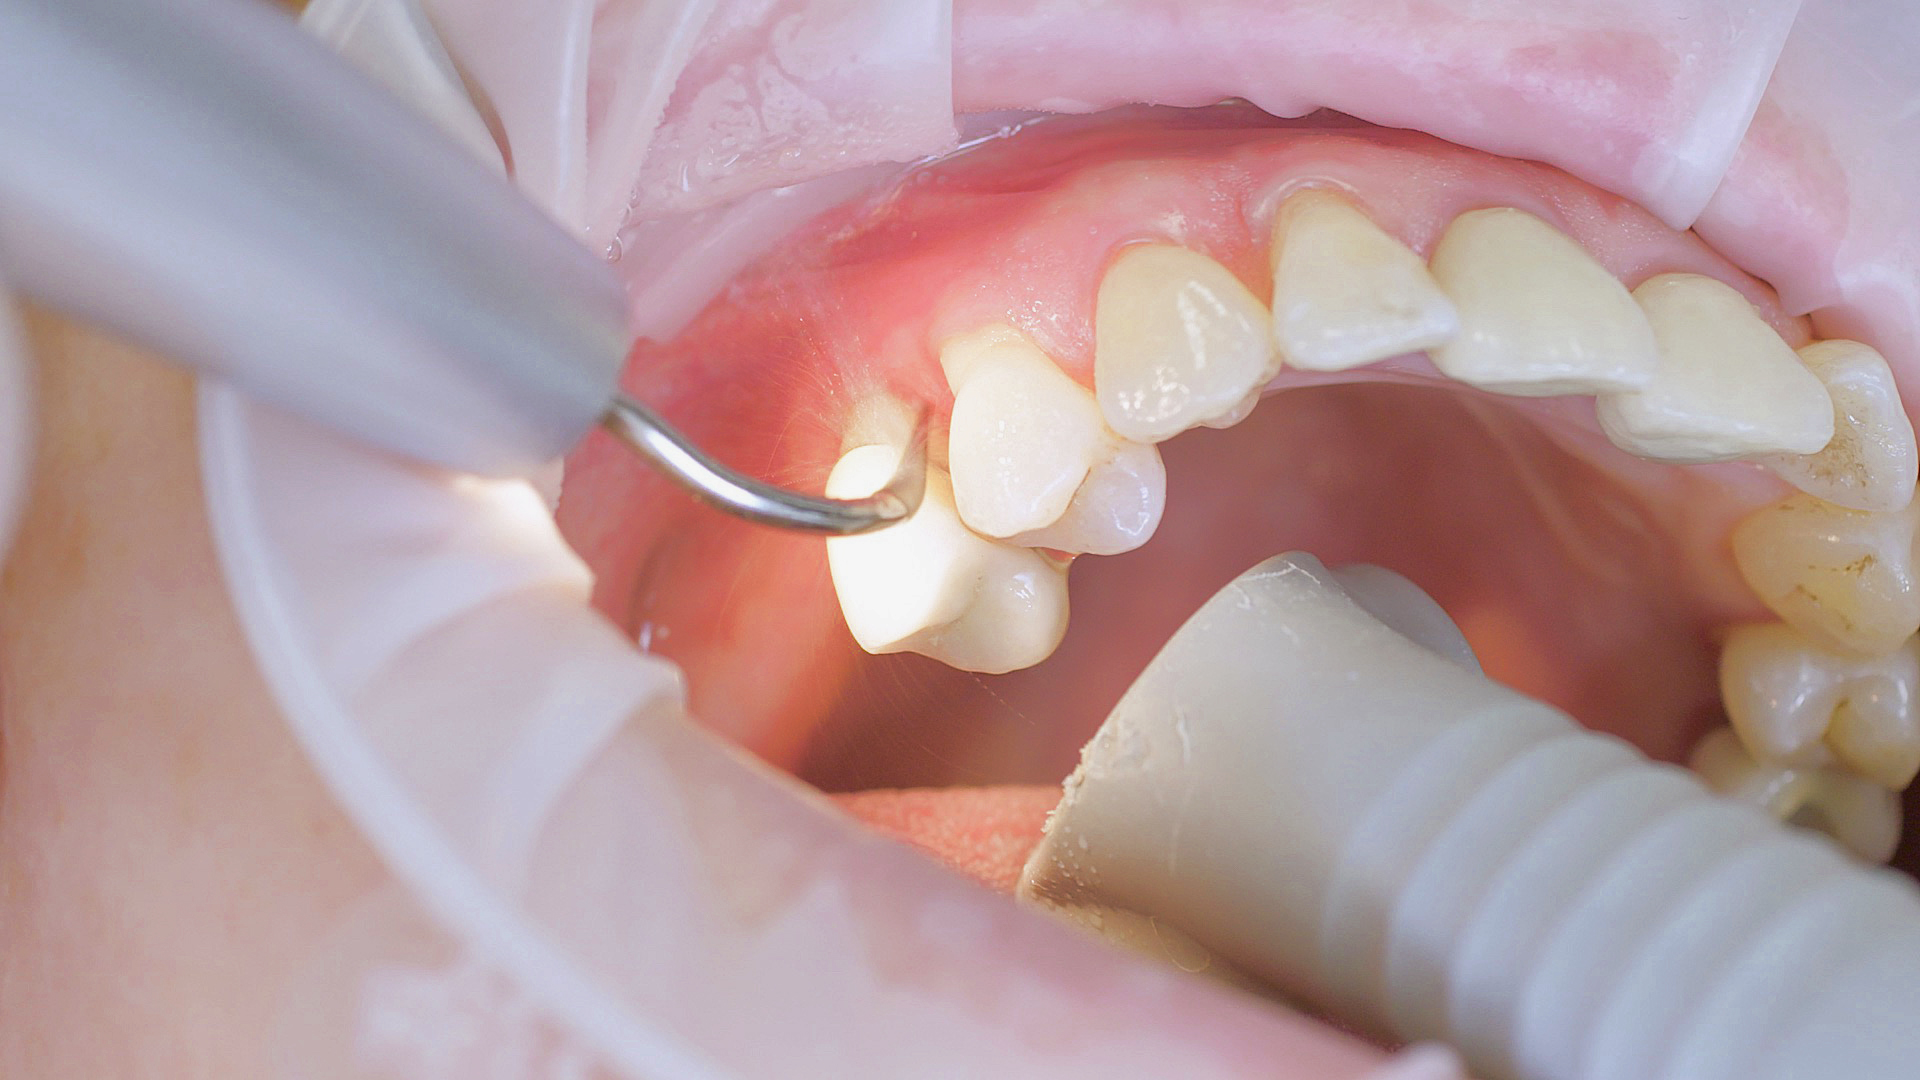

Removal of subgingival coatings (debridement) is carried out using sonic or ultrasonic devices and special periodontal tips as initial periodontal treatment (Fig. 3). Manual instruments can also be used. Further surgical and/or regenerative measures may be necessary, depending on the situation.